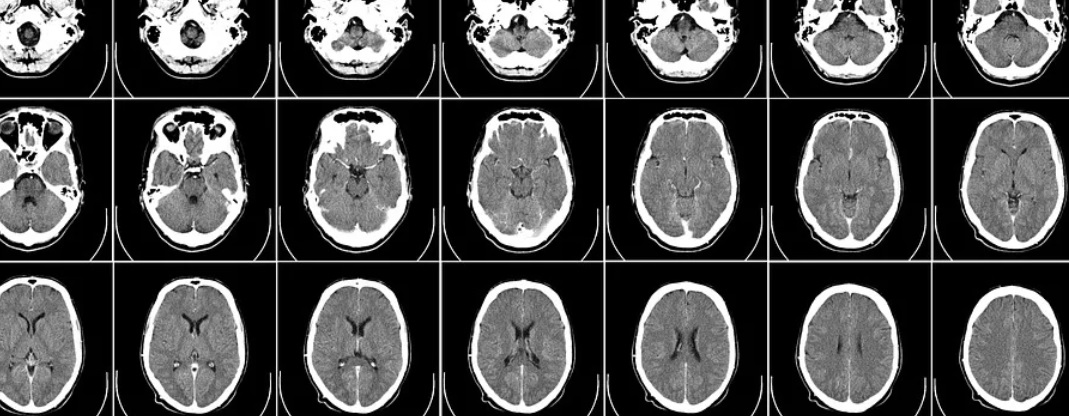

A Fluvoxamina é um inibidor seletivo da recaptação da serotonina, um neurotransmissor que atua na comunicação entre as células nervosas. Em outras palavras, o medicamento tem a capacidade de inibir o transporte da serotonina para dentro dos neurônios, o que faz com que uma maior quantidade aja sob o cérebro.